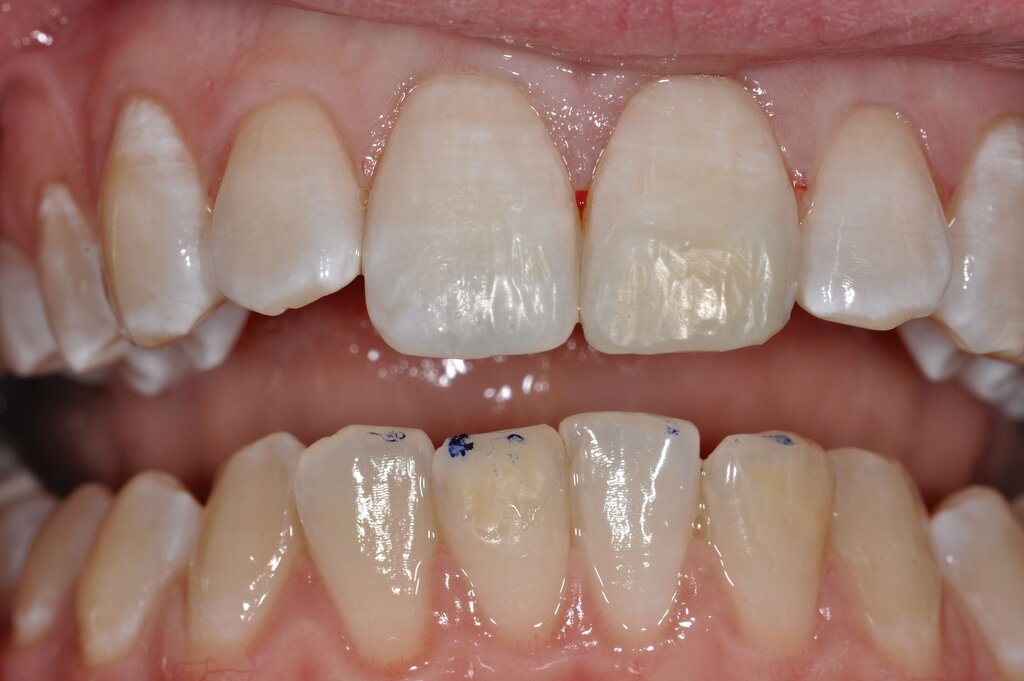

Diese Klassifikation dient als Grundlage für die Therapieempfehlungen. Deutlich wird, dass aufgrund der Symptomatik die Therapie der Zähne höchst unterschiedlich ausfällt. Dass etwa eine Opazität ohne Überempfindlichkeit (Index 1, Abbildung 1) ein anderes therapeutisches Vorgehen erfordert als ein Zahn mit nahezu komplettem Einbruch der Zahnoberfläche und mit Hypersensitivität (Index 4, Abbildung 2), ist offensichtlich.

Die Versorgung der MIH-Frontzähne entspricht dem Vorgehen im Seitenzahnbereich. Problematisch ist die Maskierung der Opazitäten. Dazu müssen opake Komposite verwendet werden und es muss eine Schichtstärke von circa 1,5 mm garantiert sein (Abbildung 9).